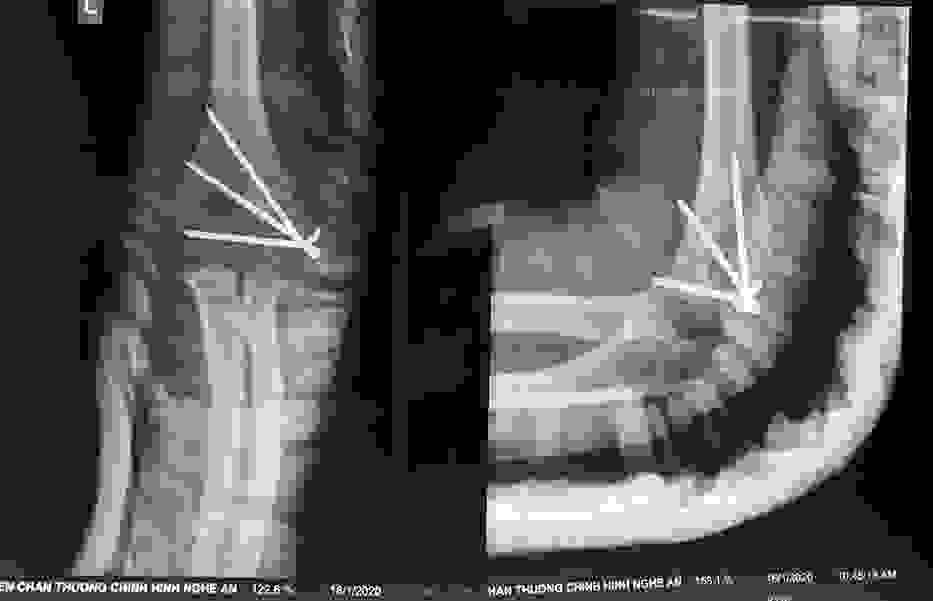

Phẫu thuật thành công ca bệnh hiếm gặp...khớp giả bẩm sinh xương chày

26/06/2019 17:00

Đã xem: 2881

Bệnh viện Chấn thương- Chỉnh hình Nghệ An, vừa phẫu thuật thành công cho bệnh nhi khớp giả bẩm sinh xương chày